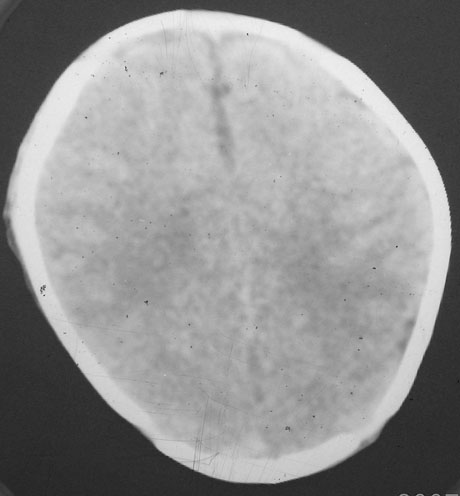

以下是引用rjg199343在2007-1-24 23:08:00的发言:[br]纵裂池、小脑幕、双侧脑室内高密度影,符合脑室、蛛网膜下腔出血。